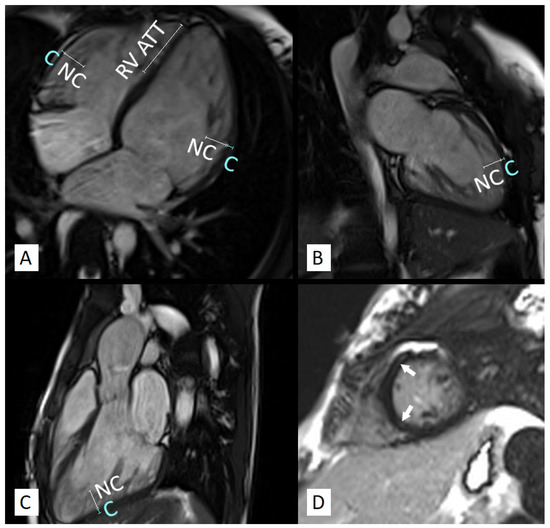

3.4. LGE in Children with LVNC

4.3. LV Fibrosis in Pediatric LVNC